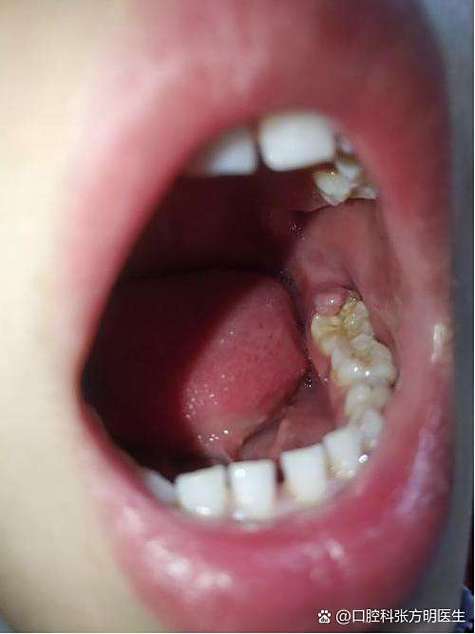

佩戴矫正器后,牙齿表面及牙龈周围容易堆积食物残渣和菌斑,传统刷牙方式难以彻底清洁托槽周围、牙龈与牙齿的交界处,长期清洁不到位会导致牙菌斑滋生,引发牙龈炎(表现为牙龈红肿、出血、易痛),若未及时处理,可能进展为牙周炎,导致牙龈肿痛加剧、牙槽骨吸收,甚至影响牙齿移动。

| 矫正中期(6个月以上) | 牙龈反复肿痛,出血明显,可能伴有牙龈增生(牙龈组织覆盖部分托槽),口臭加重。 | 加强口腔清洁,使用正畸牙缝刷清洁托槽与牙龈之间的缝隙; 每周1-2次使用含氯己定的漱口水(如复方氯己定含漱液),连续使用不超过2周; 戒烟,减少辛辣刺激性食物。 |

需及时复诊,医生可能进行专业洁治(去除牙结石)、调整矫正器或切除过度增生的牙龈。 |